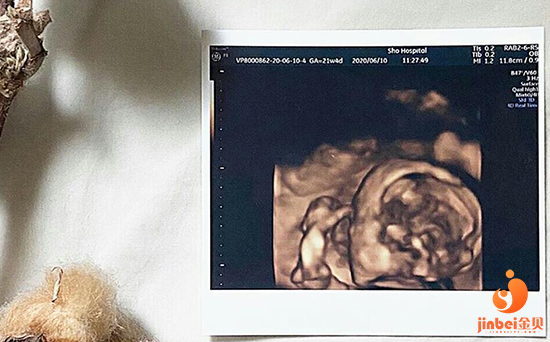

随着现在技术越来越成熟,试管婴儿的成功率跟以前比也有所提高,虽然技术发展了,成功率也提高了,但是试管婴儿的成功和女性的身体条件密不可分,越年轻,身体状态越好,成功率也就越高,年龄偏大,身体状态不佳的女性,自然成功率也低一些。那么哪些因素会导致试管婴儿失败呢?